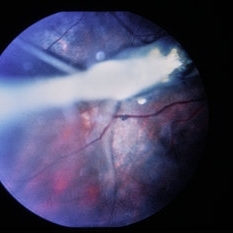

Pre-retinal and retinal hemorrhage with foreign body.

Condition/keywords: intraocular foreign body, trauma